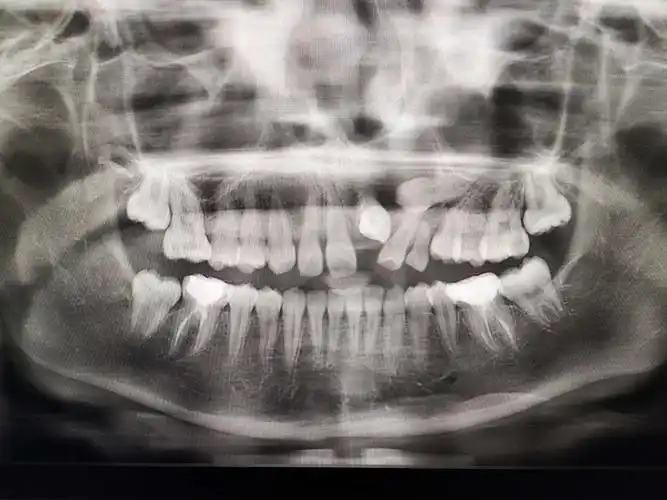

【病例】牙源性角化囊肿1例ct影像诊断

cbct检查 前牙区囊肿

口腔cbct影像分析根尖囊肿的诊断